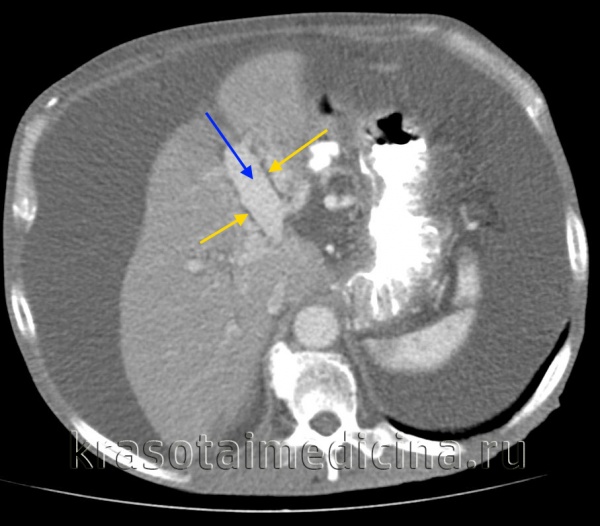

КТ ОБП. Этот же пациент, варикозно расширенные вены как проявление синдрома портальной гипертензии (коричневая стрелка).